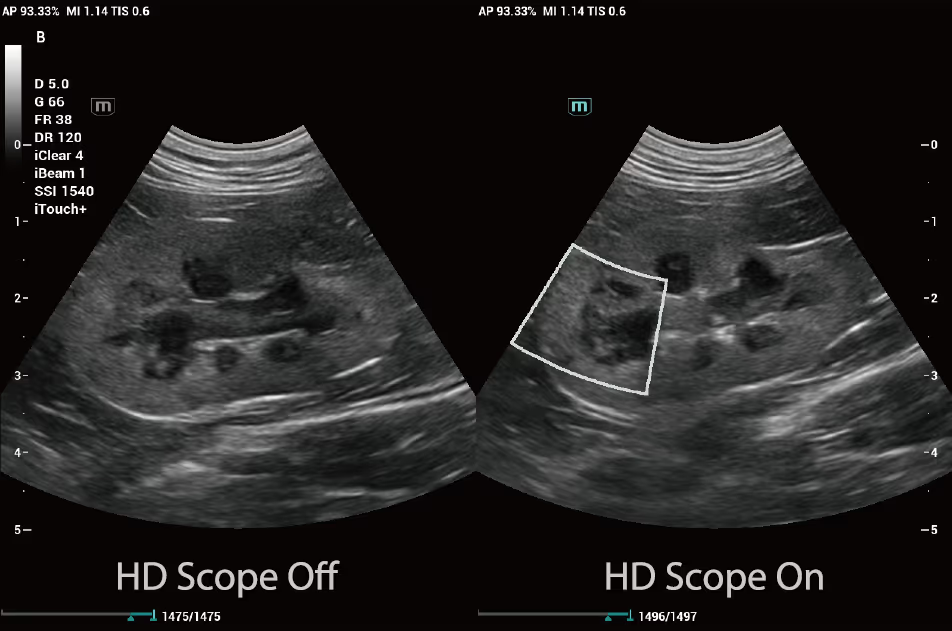

HD Scope, orijinal verileri gerçek zamanlı olarak alıp analiz edebilir. Farklı doku tiplerinin akustik özelliklerine göre farklı işleme parametreleri kullanarak, görüntüdeki detay bilgisini ve kontrastı artırır.